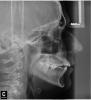

Первый приговорил к удалению все восьмерки, а также две верхних четверки чтобы было место для маневров. К тому же хирургом была приговорена к удалению семерка слева сверху (из за кариеса под десной). В итоге получается удалять 7 зубов =(

Мнение второго ортодонта более обнадеживающее: т.к. семерка слева сверху идет под удаление, то восьмерку можно не удалять, а вытянуть ее с помощью брекетов на место удаленной семерки; сверху справа под удаление пойдет либо четверка, либо пятерка (точнее скажут через неделю после составления плана лечения), а также восьмерка. Ну и восьмерки снизу можно удалять уже в процессе ортодонтического лечения.

Хочу спросить у специалистов - насколько адекватен диагноз второго врача? Стоит ли вытягивать брекетами восьмерку, или же лучше удалять?